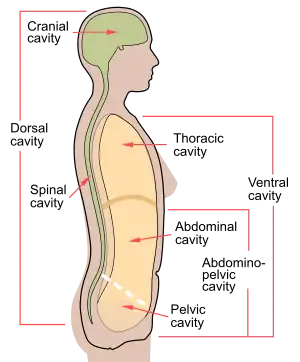

Cross-section showing cavities in the human body, the dorsal and ventral body cavities labelled. | |

The two largest human body cavities are the ventral body cavity, and the dorsal body cavity. In the dorsal body cavity the brain and spinal cord are located.

The dorsal (posterior) cavity and the ventral (anterior) cavity are the largest body compartments.

The dorsal body cavity includes the cranial cavity, enclosed by the skull and contains the brain, and the spinal cavity, enclosed by the spine, and contains the spinal cord.[1]

The ventral body cavity includes the thoracic cavity, enclosed by the ribcage and contains the lungs and heart; and the abdominopelvic cavity. The abdominopelvic cavity can be divided into the abdominal cavity, enclosed by the ribcage and pelvis and contains the kidneys, ureters, stomach, intestines, liver, gallbladder, and pancreas; and the pelvic cavity, enclosed by the pelvis and contains bladder, anus and reproductive system.[1]

The ventral cavity has two main subdivisions: the thoracic cavity and the abdominopelvic cavity. The thoracic cavity is the more superior subdivision of the ventral cavity, and is enclosed by the rib cage. The thoracic cavity contains the lungs surrounded by the pleural cavity, and the heart surrounded by the pericardial cavity, located in the mediastinum. The diaphragm forms the floor of the thoracic cavity and separates it from the more inferior abdominopelvic cavity.

The abdominopelvic cavity is the largest cavity in the body occupying the entire lower half of the trunk. Although no membrane physically divides the abdominopelvic cavity, it can be useful to distinguish between the abdominal cavity, and the pelvic cavity. The abdominal cavity occupies the entire lower half of the trunk, anterior to the spine, and houses the organs of digestion. Just under the abdominal cavity, anterior to the buttocks, is the pelvic cavity. The pelvic cavity is funnel shaped, and is located inferior and anterior to the abdominal cavity, and houses the organs of reproduction.[2]

Dorsal body cavity

The dorsal body cavity contains the cranial cavity, and the spinal cavity. The cranial cavity is a large, bean-shaped cavity filling most of the upper skull where the brain is located. The spinal cavity is the very narrow, thread-like cavity running from the cranial cavity down the entire length of the spinal cord.

In the dorsal cavity, the cranial cavity houses the brain, and the spinal cavity encloses the spinal cord. Just as the brain and spinal cord make up a continuous, uninterrupted structure, the cranial and spinal cavities that house them are also continuous. The brain and spinal cord are protected by the bones of the skull and vertebral column and by cerebrospinal fluid, a colorless fluid produced by the brain, which cushions the brain and spinal cord within the dorsal body cavity.[2]

The lungs, heart, stomach, and intestines, for example, can expand and contract without distorting other tissues or disrupting the activity of nearby organs.[2] The ventral cavity includes the thoracic and abdominopelvic cavities and their subdivisions. The dorsal cavity includes the cranial and spinal cavities.[2]